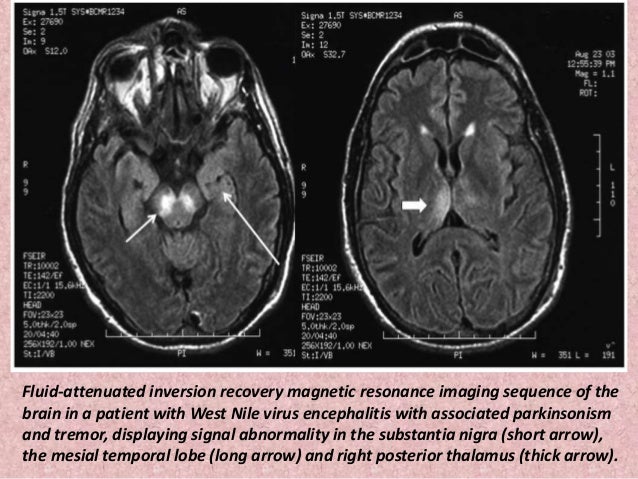

However the primary use of mr imaging is to exclude specific structural abnormalities that could potentially mimic parkinson disease eg normal pressure. Share on pinterest an mri or ct scan can help to distinguish parkinson s from other conditions that may have similar symptoms such as a stroke. Fdg pet uptake can demonstrate patterns of neuronal dysfunction that are specific to a particular parkinsonian syndrome. In advanced disease abnormalities of the substantia nigra including volume loss decreased t2 signal reflecting iron deposition and blurring of the margins can be seen 26 28.